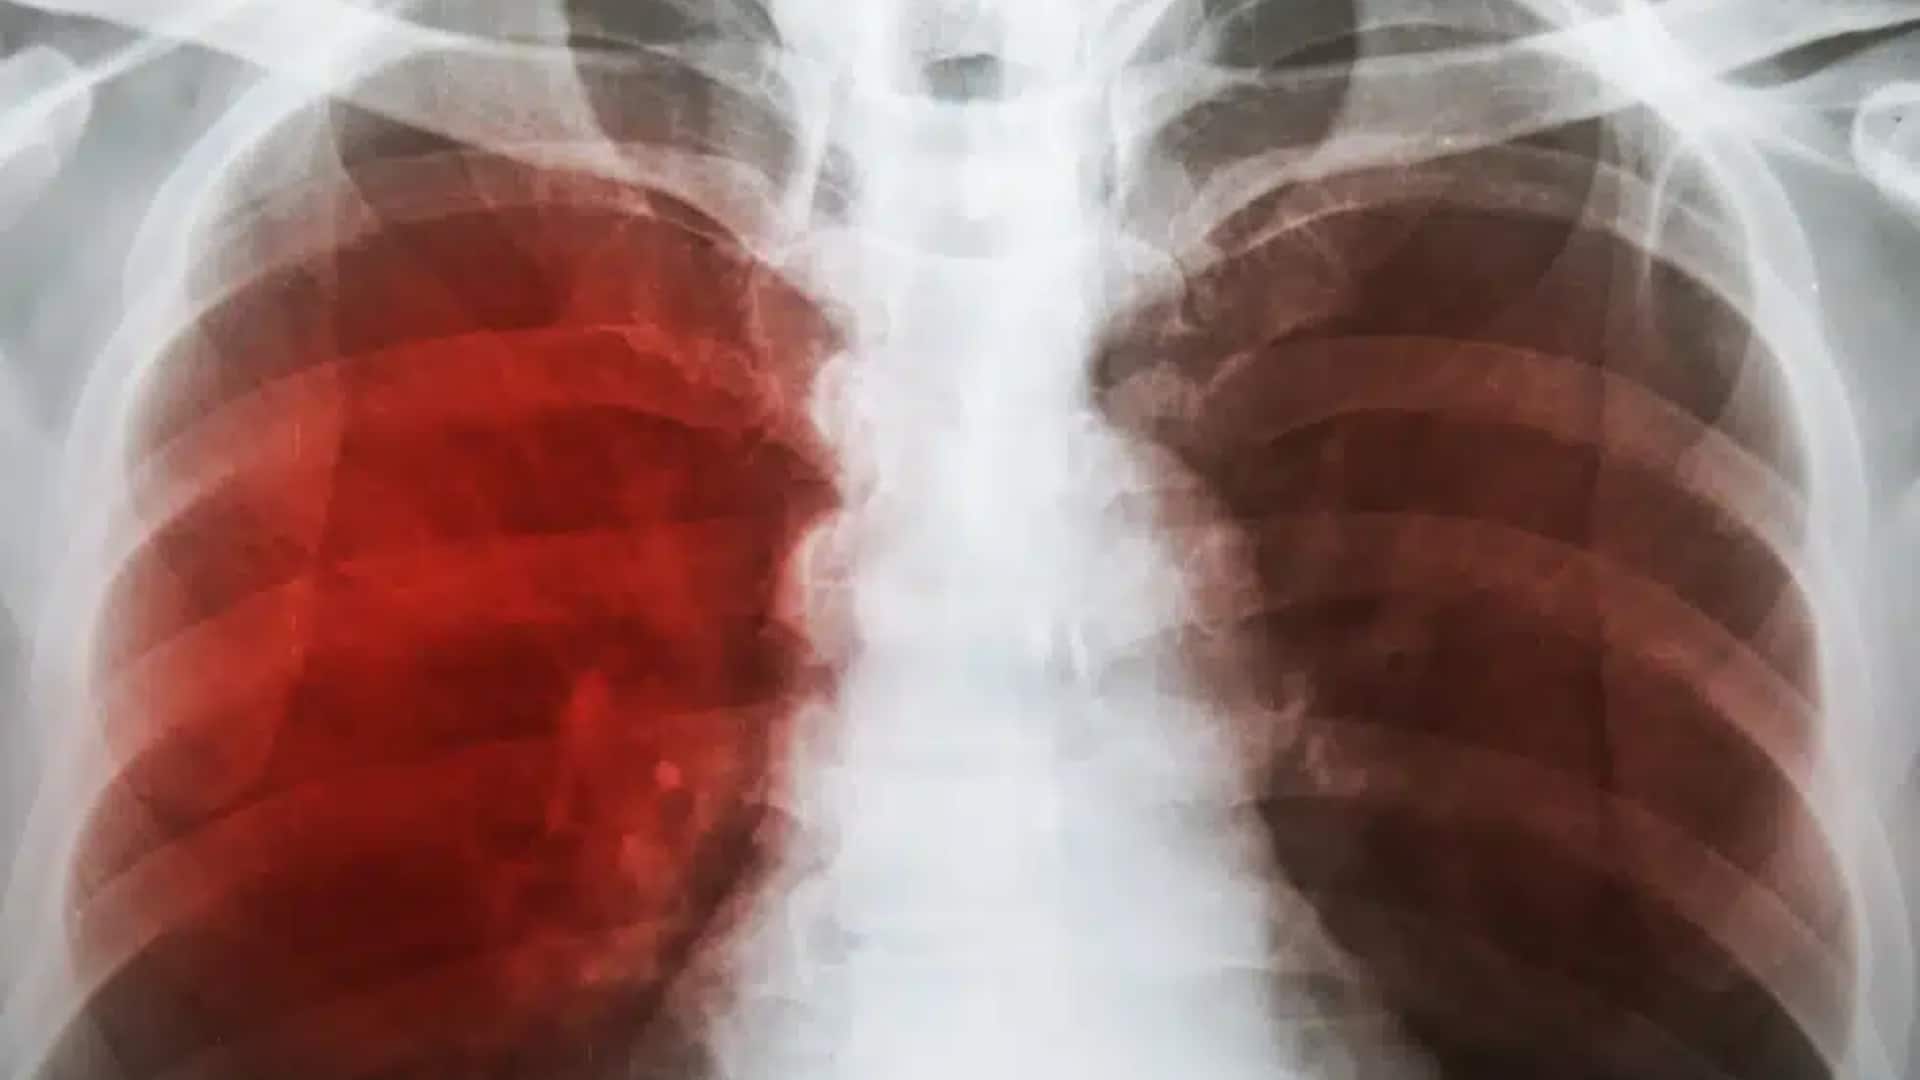

Қостанай облысында Меңдіқара ауданы орталығындағы гимназияда туберкулез ошағы пайда болғаны белгілі болды.

Наурыз айының алғашқы онкүндігінде Боровское ауылындағы Ғаббас Жұмабаев атындағы гимназия асханасына жұмысқа алынған әйелден туберкулез анықталған. Соған орай оқу орны қашықтан оқытуға жабылғанын хабарлаған еді.

Меңдіқара ауданы әкімдігінің білім бөлімінің басшысы Гүлдана Ахметованың мәліметінше, 5-6 наурыз күндері білім беру мекемесінің 94 қызметкері міндетті медициналық тексеруден өткен. 10–15 наурыз аралығында 315 оқушыға туберкулиндік диагностика жүргізіліп, 16 наурызда медицина қызметкерлері нәтижелерін тексерген. Қорытындысында оқушылар мен мұғалімдерден туберкулез белгілері анықталмаған.